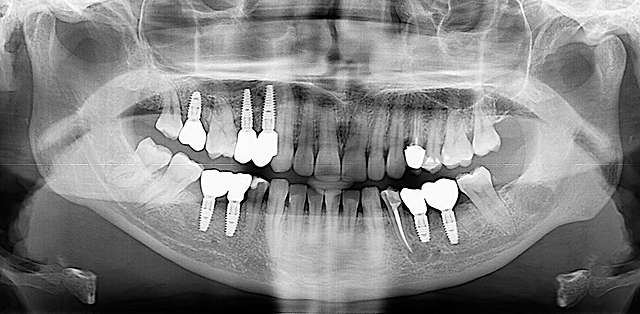

Ghidurile chirurgicale sunt utilizate pentru o siguranta si o precizie sporita in cazurile complexe care necesita tratamentul cu implanturi dentare. Ghidurile sunt printate 3D, conform planificarii digitale a chirurgiei, folosind un software specializat si radiografia 3D a pacientului. (computerul tomograf)

Pentru un rezultat estetic ideal, design-ul final trebuie sa fie intotdeauna referinta pentru chirurgie. Design-ul si computerul tomograf al pacientului sunt compilate pentru a primi pozitia ideala a implanturilor dentare

Chirurgia ghidata este sigura si precisa. Ghidul chirurgical este recomandat in cazurile cu un nivel ridicat de dificultate, sau in cazurile complexe, pentru a minimiza riscurile si complicatiile.

Cand procedura insertiei implanturilor dentare se realizeaza cu ajutorul chirurgiei ghidate, chirurgia in sine este mai simpla, iar trauma este mai redusa, in special asupra tesuturilor moi. Astfel, obtinem o vindecare mai rapida, si un comfort sporit post operator.